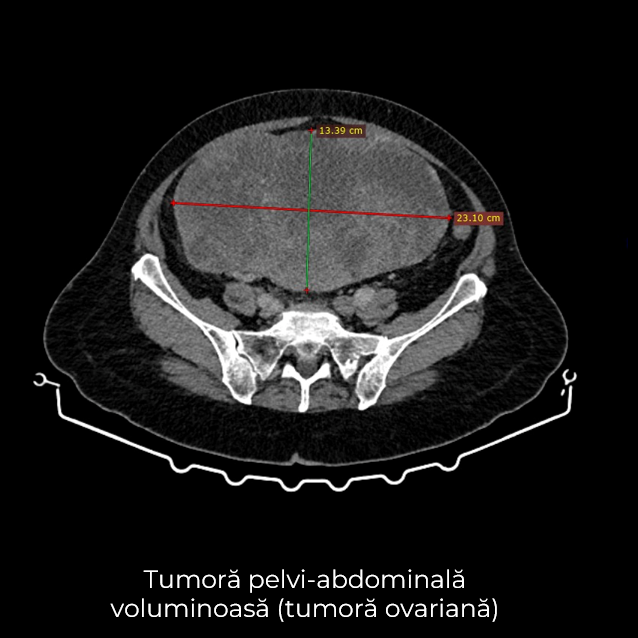

Uneori, o durere aparent banală ascunde în spate o realitate medicală mult mai serioasă. Așa s-a întâmplat și în cazul unei paciente de 63 de ani, care a ajuns la spital pentru dureri pelvine persistente. Investigația CT a schimbat însă complet perspectiva: au fost descoperite trei formațiuni tumorale în zone diferite ale corpului – o tumoră mamară stângă (carcinom mamar invaziv biopsiat), o tumoră pelvi-abdominală voluminoasă (tumoră ovariană) și o formațiune la nivelul peretelui posterior gastric (leiomiom gastric biopsiat).

- Histerectomie totală cu anexectomie bilaterală – îndepărtarea uterului și a ovarelor, cu verificarea histopatologică intraoperatorie a tumorii ovariene ce a relevat carcinom ovarian, limfadenectomie pelvină și interaortico-cava, omentectomie, biopsii peritoneale multiple.